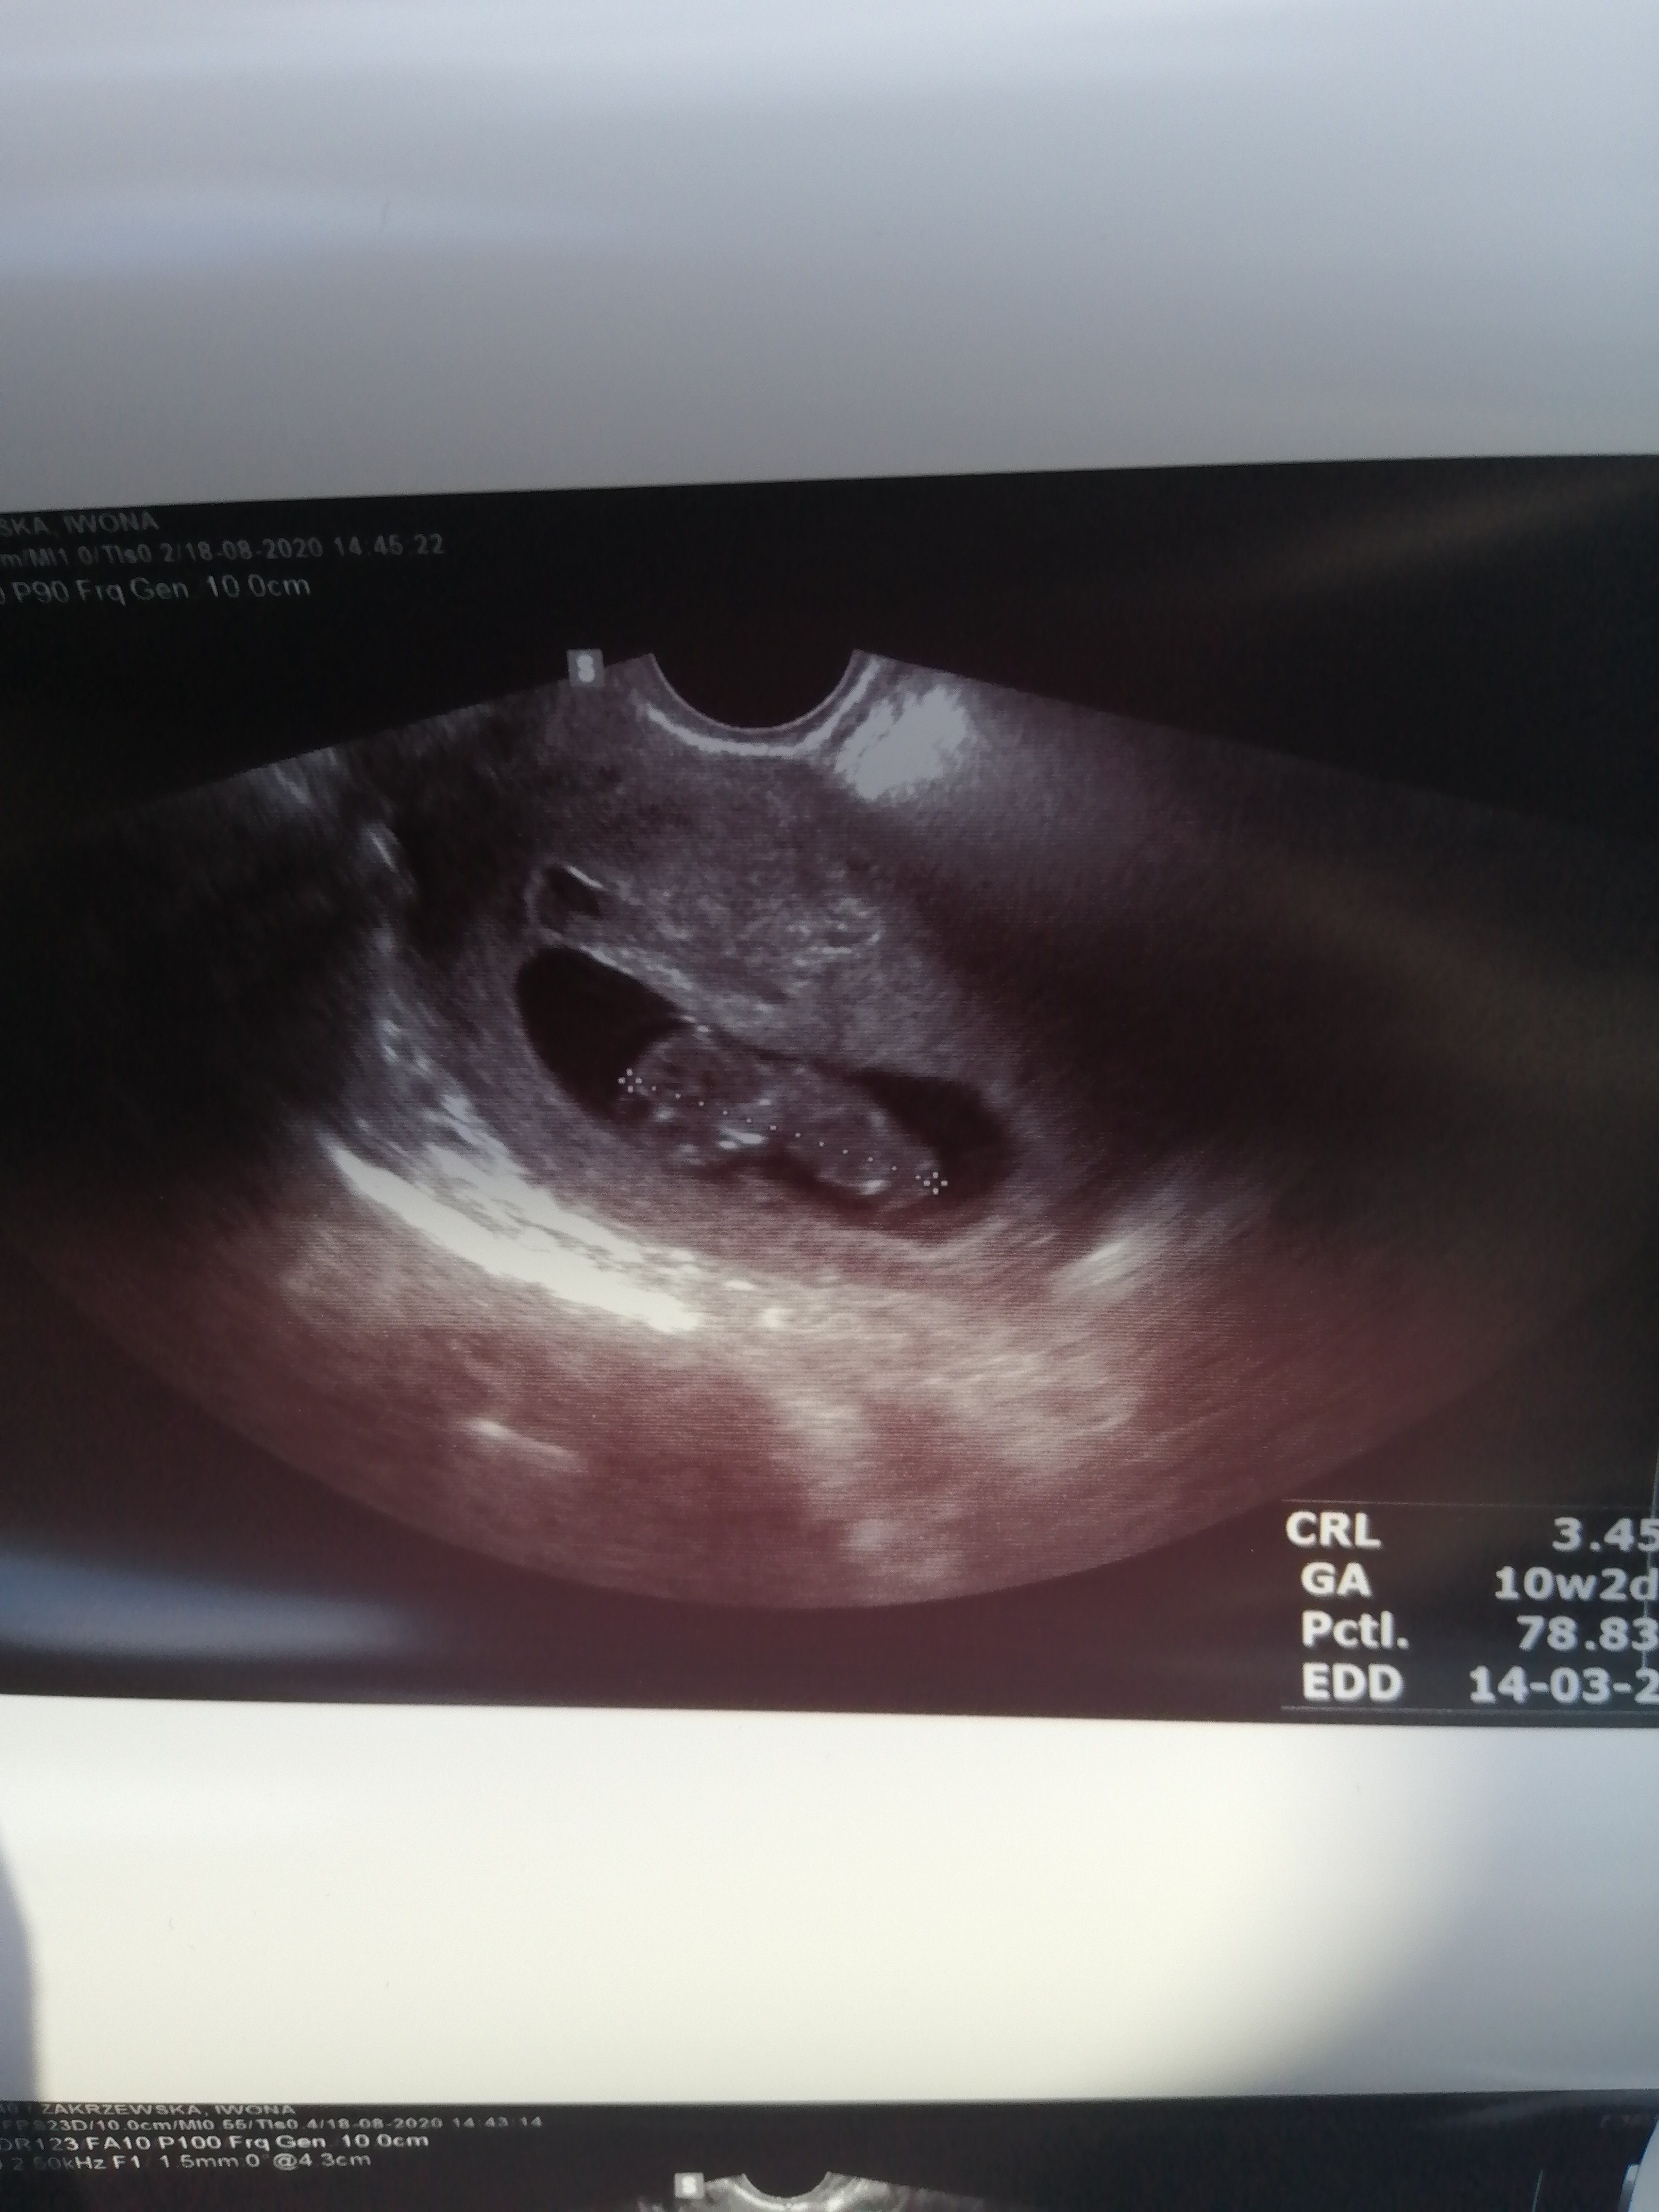

Ja jestem juz po wizycie. Wszystko w porządku bobo sie wywijał na wszystkie strony i nie mógł lekarz złapać crl

wkoncu udalo sie i oto moje dzieciątko, z usg wychodzi 10w2 d a z OM 9w5d 4 dni roznicy sie zdziwilam ze az tak w gore idzie

tętno 174 i to mnie niesamowicie cieszy identycznie jak 2 tygodnie temu.